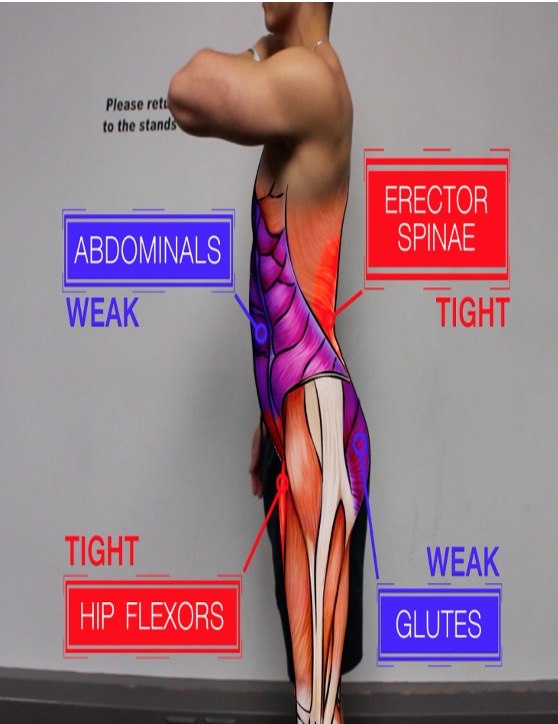

- 与骨盆有关的常见烦恼就是骨盆“歪斜”。而骨盆之所以歪斜,是因为肌肉不平衡,而并非骨骼本身变形。 最近经常有产后妈妈咨询,说自己骨盆歪了,我们有什么仪器帮助她,听说某某机构一次正骨就好了。听的我一头雾水,作为康复治疗师,从人体解剖结构上来讲我认为这些都是营销噱头,因为除去疾病状态骨骼本身并不会歪.....

- 布骨医学科普:为什么骨盆会产生歪斜? 布骨康复医疗中心董月 ,2020-07-11

- 引起骨盆歪斜的原因: 1. 扭伤、受伤没有痊愈,带着旧伤继续行走生活; 2. 先天性的O型腿、扁平足、加上体重过重、运动过度所致; 3. 长时间跷二郎腿,驼背坐姿电脑前办公; 4. 腹肌、背肌力量弱,坐椅子时没有坐到底,但又喜欢靠着椅背; .....